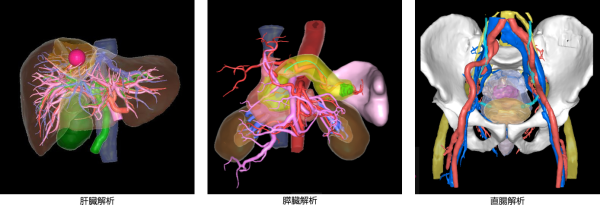

今回提供を開始する「SYNAPSE VINCENT Ver7.0」では、より立体感のある3D画像を描出する「新レンダリング技術(Order Independent Transparency)」を採用し、3D画像の視認性を向上させた。また、肝臓および周辺臓器を変形させながら血管走行などを観察できる「+肝臓変形機能」を搭載し、術前に肝臓を切除する術式のシミュレーションを行うことが可能だ。さらに、「治療で改善できる認知症」と言われ早期発見が重要なハキム病(特発性正常圧水頭症:iNPH)の診断に寄与することが期待される「脳脊髄液腔解析」も搭載した。加えて、ソニー株式会社が開発した「空間再現ディスプレイ」と連携することで、「SYNAPSE VINCENT」で作成した術前シミュレーション用画像を裸眼で立体的に観察できる。主な機能は以下の通り。

手前から奥側へ順に色を混合する新レンダリング技術を用いることで、従来よりも奥行方向への視認性を向上させた3D画像を描出できる。これにより臓器と血管の位置関係を把握しやすくなる。

肝臓の術前シミュレーションを支援する「肝臓解析」と組み合わせて使用する「+肝臓変形機能」は、肝臓の3D画像に対して肝臓および周辺臓器を変形させながら観察することができる。術前に肝臓を切除する術式のシミュレーションを直観的な操作で行うことが可能で、手術時に切除する際の各脈管の位置推定をサポートする。

術前シミュレーションを支援する「肝臓解析」や「膵臓解析」など8つの解析機能をシンプルかつ直観的に操作できる「Quickモード」に切り替えて使用できる。従来のユーザーインターフェースでの操作と比較して簡便かつ迅速に解析を行うことができる。